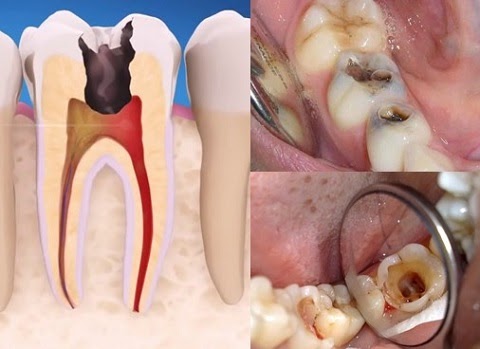

Bọc răng sứ có phải lấy tủy răng không?